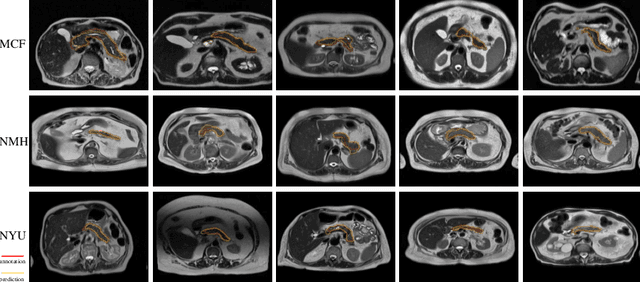

Abstract:Federated learning (FL) enables collaborative model training across institutions without sharing sensitive data, making it an attractive solution for medical imaging tasks. However, traditional FL methods, such as Federated Averaging (FedAvg), face difficulties in generalizing across domains due to variations in imaging protocols and patient demographics across institutions. This challenge is particularly evident in pancreas MRI segmentation, where anatomical variability and imaging artifacts significantly impact performance. In this paper, we conduct a comprehensive evaluation of FL algorithms for pancreas MRI segmentation and introduce a novel approach that incorporates adaptive aggregation weights. By dynamically adjusting the contribution of each client during model aggregation, our method accounts for domain-specific differences and improves generalization across heterogeneous datasets. Experimental results demonstrate that our approach enhances segmentation accuracy and reduces the impact of domain shift compared to conventional FL methods while maintaining privacy-preserving capabilities. Significant performance improvements are observed across multiple hospitals (centers).

Abstract:Intraductal Papillary Mucinous Neoplasm (IPMN) cysts are pre-malignant pancreas lesions, and they can progress into pancreatic cancer. Therefore, detecting and stratifying their risk level is of ultimate importance for effective treatment planning and disease control. However, this is a highly challenging task because of the diverse and irregular shape, texture, and size of the IPMN cysts as well as the pancreas. In this study, we propose a novel computer-aided diagnosis pipeline for IPMN risk classification from multi-contrast MRI scans. Our proposed analysis framework includes an efficient volumetric self-adapting segmentation strategy for pancreas delineation, followed by a newly designed deep learning-based classification scheme with a radiomics-based predictive approach. We test our proposed decision-fusion model in multi-center data sets of 246 multi-contrast MRI scans and obtain superior performance to the state of the art (SOTA) in this field. Our ablation studies demonstrate the significance of both radiomics and deep learning modules for achieving the new SOTA performance compared to international guidelines and published studies (81.9\% vs 61.3\% in accuracy). Our findings have important implications for clinical decision-making. In a series of rigorous experiments on multi-center data sets (246 MRI scans from five centers), we achieved unprecedented performance (81.9\% accuracy).